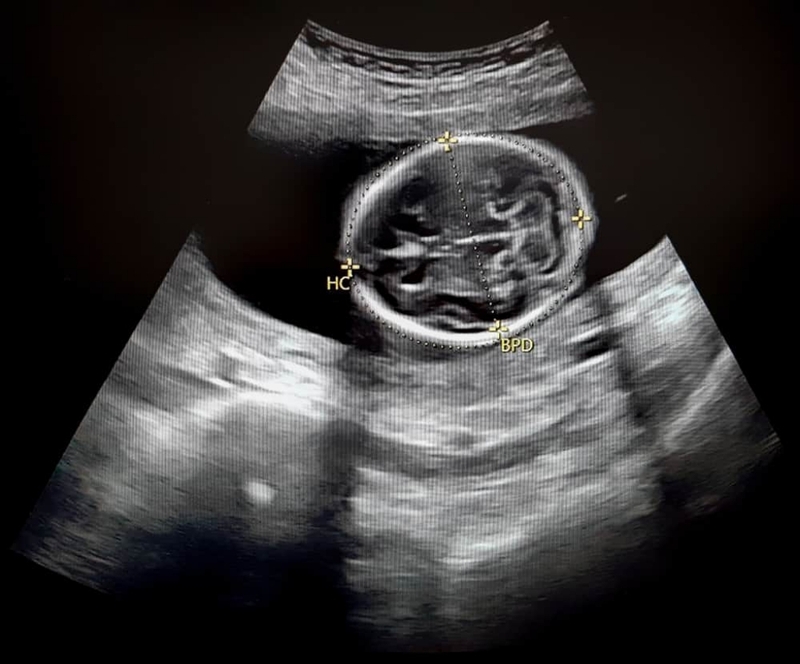

Chu vi vòng đầu thai nhi, thường ký hiệu là HC (Head Circumference), đây là một phép đo sinh trắc học, được sử dụng như một chỉ số tiêu chuẩn để đánh giá kích thước đầu của trẻ có thuộc giới hạn bình thường so với tuổi thai hay không.

HC là một phần không thể thiểu trong các mô hình siêu âm. Thông qua HC bác sĩ có thể theo dõi tình trạng phát triển của trẻ qua từng tuần thai và qua đó để phát hiện những dấu hiệu bất thường mà thai nhi có thể gặp phải. Bên cạnh đó, dựa vào chỉ số HC bác sĩ sẽ tư vấn phương thức chuyển dạ cho mẹ bầu nên sinh thường hay sinh mổ.

Xác định chu vi vòng đầu thường thông qua các phép đo siêu âm thai. Chỉ số siêu âm có vai trò quan trọng giúp cho việc chẩn đoán tình trạng thai nhi.

• Đường kính lưỡng đỉnh (BPD).

Hình ảnh siêu âm giúp ích trong việc chẩn đoán sức khỏe thai nhi. Qua đó phát hiện những nguy cơ tiềm ẩn của mẹ và thai nhi. Thông thường, chu vi vòng đầu sẽ được chẩn đoán qua siêu âm bắt đầu từ tuần thứ 12 trở đi. Trọng lượng thai cũng được ước lượng qua các phép tính toán những chỉ số này.

Chu vi vòng đầu thai nhi là gì? Chỉ số quan trọng tới sức khỏe mẹ và bé 2 Xác định HC thông qua các phép đo siêu âm

Theo từng tuần thai, chu vi vòng đầu thai nhi có sự thay đổi. Ở những bé có cùng tuổi thai cũng sẽ có sự khác biệt về chỉ số này. Bác sĩ thường xác định chỉ số HC theo bảng được nghiên cứu trước đó, từ đó chẩn đoán tỷ lệ phát triển cũng như mức độ nguy cơ mắc dị tật ở trẻ.